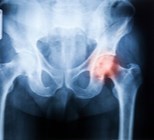

שחיקת מפרק הירך כרוכה בכאב ובהגבלת תנועה ועלולה להתרחש גם...